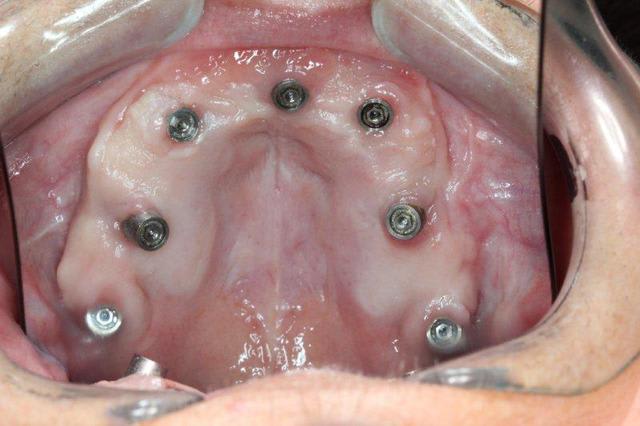

P'tite question, les vis qui tiennent la prothèse en place, sont des vis " plates", simple rainure.

L'axe de certains implants semble un peu trop palatin, mais bon, il n'y a pas de nonos...

J'aimerais voir l'hygiène dans 1-2 ans...

1. C est toi qui es malhabile... Rien de plus simple : tu mets ttes tes vis ds la puits, tu les recouvres d homéoplasmine pour les empêcher de tomber hors des puits, tu poses en bouche et tu passes ton tournevis ds homéoplasmine pour visser Très simple et très efficace :-))))

2. Effectivemeznt les plaques zygomatiques ont des émergences palatines mais au définitif j ai ôté les piliers prlongateurs de 3.5 mm et du coup même si sortie palatine plus aucun "débordement" du puits de vissage en dehors de l arcade...

3.Ca fait 18 mois que les implants sont en charge donc tu as déjà une idée mais de manière générale ça fonctionne aussi bien qu pilotis à la mandibule... Un petit coup de waterpik léger et qques bains de bouches suffisent à entretenir tout ça correctement

De tte façon si tu fais pas ce que je viens de faire, tu es cuit pour deux sinus-lifts ( dont la patiente ne voulait pas !!!!! )et encore tu n auras aucun implant au delà des 4 voire des 3 donc un terrible porte-à-faux devant... Sinon tu dois ajouter un Lefort pour interposer un bloc au niveau incisif... Elle refuse encore plus le Lefort que les sinus-lifts

PS Cette résorption est le résultat du port d un amovible complet de 30 ans à 63 ans ...

Regarde le provisoire de la MCI : les émergences des plaques au niveau molaires font des bombés hors arcades suite à la pose de piliers monobloc de hauteur 3.5 mm

On pose ces piliers car il faut pouvoir retrouver facilement les têtes d implants 72 h plus tard pour poser la prothèse de transition